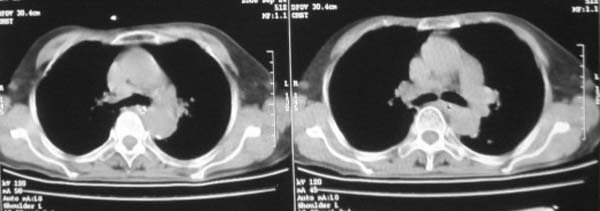

女,78岁,声嘶月余,否认有既往病史,有粉尘接触史10年。

颈部见多枚淋巴结肿大,考虑尘肺继发结核,喉部淋巴结钙化,不除外喉部慢性淋巴结炎、喉淀粉样变及类癌等

肺癌伴纵膈、双颈部淋巴结转移;尘肺。

右上肺癌伴肺内转移及纵隔淋巴转移 左上肺结核 图像有点模糊

双上肺结节融合影,周围有纤维条索影,结合粉尘接触史,首先考虑尘肺。双侧颈部有增大淋巴结,有声嘶表现,肺癌淋巴结转移不能排除。可结合颈部淋巴结活检。